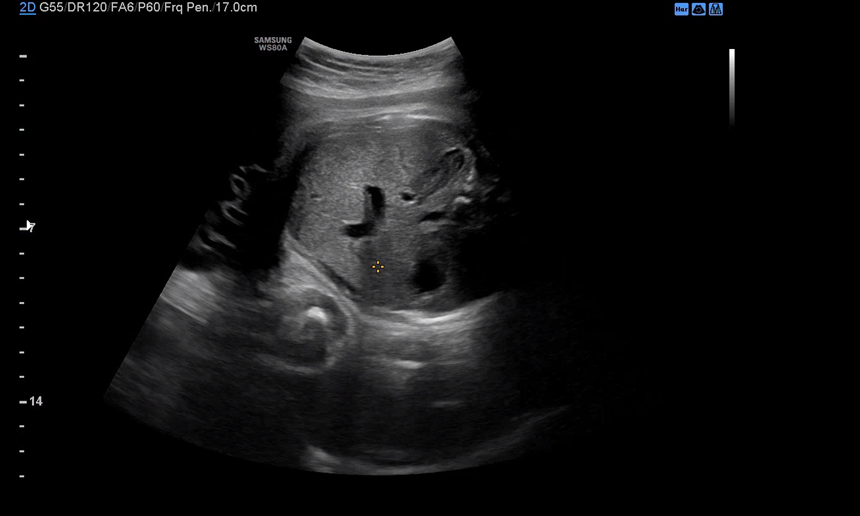

막달 검사를 마치고 30분 정도 대기한 뒤 원장을 진료를 봤다. 4분가량 배 초음파로 아기의 상태를 체크해주시는데 BPD, Fetal HR, AC, FL 순서로 봐주시고 마지막으로 아기 얼굴을 보여주셨다.

배 초음파를 마치고 질 균 검사를 하면서 자궁경부 길이도 다시 재주셨다. 지난번엔 자궁경부 길이가 오히려 좀 남는다고 하셨는데 이번엔 꽤 내려와 있었다. 입원하거나 너무 걱정할 정도로 내려온 건 아니고 지금쯤 이 정도는 내려와야 분만할 수 있다고 그러셨다. 배뭉침도 이 시기는 너무 없어도 분만이 어려울 수 있다고 지금 느끼는 불편함과 통증은 자연스러운 거라고 안심시켜주셨다. 그래도 피 비침이 있으면 바로 병원에 와야 한다고 말씀하셨던 거 같다. 이제 다음 진료는 37주 차에 방문하게 되는데 임산부로서 진료 보는 날이 이제 얼마 남지 않았다. 남은 기간 동안 조금 더 마음을 내려놓고 편히 지내도록 노력할까 한다.